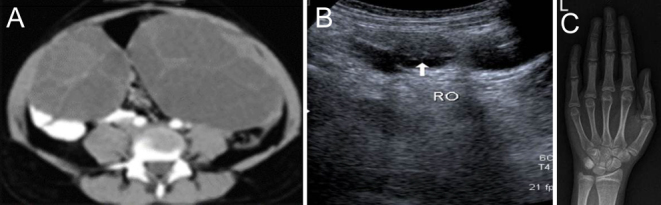

Summary: Ovarian hyperstimulation syndrome (OHSS) usually occurs in patients undergoing assisted reproduction techniques and ovulation induction. Its variant, spontaneous ovarian hyperstimulation syndrome, a potentially life-threatening disorder, is uncommon and only a few cases have been reported in association with hypothyroidism. This study analysed five patients with untreated chronic hypothyroidism presenting with multicystic ovaries, isosexual precocious puberty, and delayed bone age; subsequently, the follow-up and regression of ovarian pathology was assessed. Two patients had presented to the emergency department with menorrhagia and hypotension, of these, one had ovarian torsion at presentation. Three patients presented to the outpatient department: one for evaluation of short stature, one for premature menarche, and another with polycystic ovaries. They were all diagnosed with long-standing, untreated chronic hypothyroidism. There was regression of the size of the cystic ovaries on subsequent follow-up. In all these patients, long-standing hypothyroidism had resulted in ovarian hyperstimulation syndrome. The potentially life-threatening complications of this syndrome may be prevented by careful screening and a strong index of clinical suspicion at the outset.

Learning points: Long-standing, untreated primary hypothyroidism may result in spontaneous ovarian hyperstimulation syndrome. A high index of suspicion is required for an early and accurate diagnosis. The requirement for interdepartmental collaboration between gynaecology and endocrinology departments is essential for the successful management of this life-threatening but easily treatable disorder.